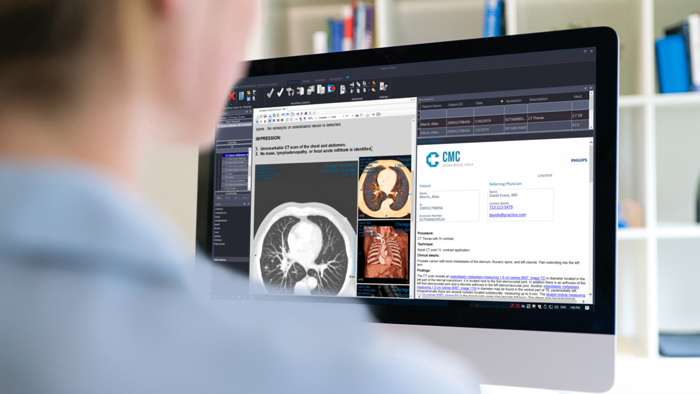

Reporting and results communication

Integrated, AI-driven enterprise scalable platforms for smart reading and reporting.